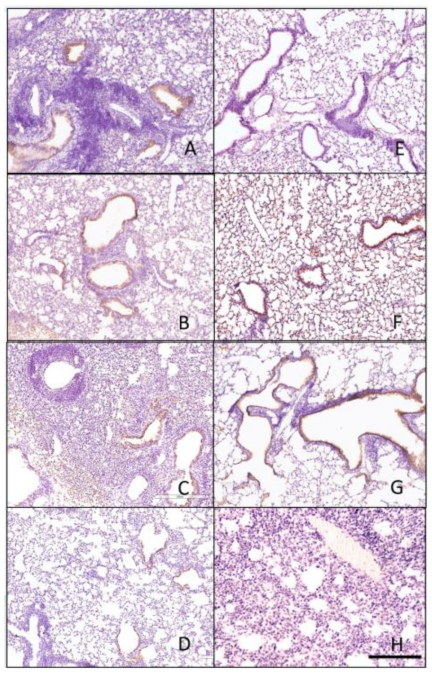

3.4. Histopathology